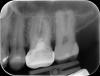

Гость Vini Vidi Vici Опубликовано 30 июня, 2008 Поделиться Опубликовано 30 июня, 2008 Как по вашему, какая перспектива у этого зуба?..... "эндо" делалось 12 лет назад Есть деструкция костной ткани в межкорневом периодонте. А почему спрашиваете, каково моё мнение? Ссылка на комментарий

Fred Опубликовано 30 июня, 2008 Поделиться Опубликовано 30 июня, 2008 (изменено) Есть деструкция костной ткани в межкорневом периодонте. А почему спрашиваете, каково моё мнение? Ой, да таких "деструкций" в каждом зубе при желании можно увидеть. На фоне корня деструкцию костной ткани заметить - это уж слишком сложно. Стрелочкой укажите, где Вы ее увидели? Лучше обратите внимание на рентгенонеконтрастные каналы, что подразумевает их пустоту и потенциальную опасность для апикального периодонта. Для Инспирейшн. Я понял, мы по-разному понимали слово "маскирует", теперь все ясно, я согласен Изменено 30 июня, 2008 пользователем Fred Ссылка на комментарий

Гость Vini Vidi Vici Опубликовано 30 июня, 2008 Поделиться Опубликовано 30 июня, 2008 Ой, да таких "деструкций" в каждом зубе при желании можно увидеть. На фоне корня деструкцию костной ткани заметить - это уж слишком сложно. Стрелочкой укажите, где Вы ее увидели? Лучше обратите внимание на рентгенонеконтрастные каналы, что подразумевает их пустоту и потенциальную опасность для апикального периодонта. Для Инспирейшн. Я понял, мы по-разному понимали слово "маскирует", теперь все ясно, я согласен Я видела много рентгеноконтрастных каналов, что подразумевает их наполненность-и активную опасность для периодонта в виде кисты апикального и межкорневого периодонта с последующим удалением вышеупомянутых зубов. А в данном случае я только проИМХОтепила. Это касается снимка Bosa. Ссылка на комментарий

Гость Vini Vidi Vici Опубликовано 6 июля, 2008 Поделиться Опубликовано 6 июля, 2008 Как по вашему, какая перспектива у этого зуба?..... "эндо" делалось 12 лет назад А перспектива у РФ-зубов одна-удаление.Попытки перелечить часто безуспешны, и после n-ного количества эндоманипуляций с зубом приходится расставаться. Ссылка на комментарий